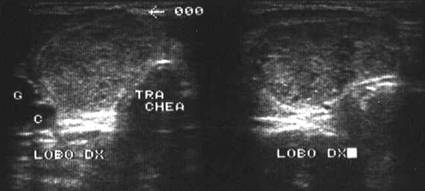

Tiroida normala

Ecostrutura omogena, normoecogena. Dimensiuni normale.

Se urmaresc rapoartele cu carotida, jugulara, muschii, traheea, esofagul.